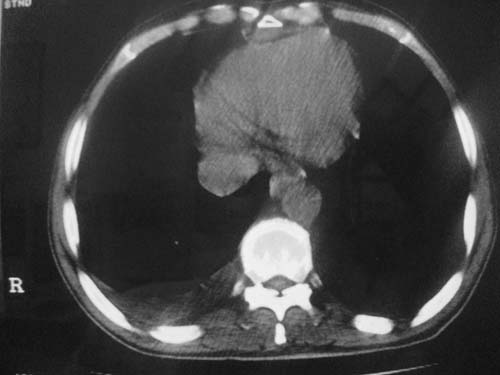

以下是引用科室第一人在2010-3-25 20:30:00的发言:[br]1:纵膈肿瘤性病变,恶性胸腺瘤可能性大伴纵膈右肺门淋巴结转移,右侧胸腔积液。[br]2:右侧肺门肿瘤性病变,纵膈淋巴结转移,右侧胸腔积液。右下叶转移。

以下是引用子期在2010-3-25 21:00:00的发言:[br]先考虑右中央型肺癌伴转移。

以下是引用江广1996在2010-3-25 22:49:00的发言:[br]通常肺癌向纵隔转移多见,纵隔肿瘤向肺内转移少见(有的表现为向肺内侵润)。本例以一元论考虑:右中心型肺癌并纵隔淋巴等多处转移。[br][br][本贴已被 江广1996 于 2010-3-25 22:50:07 修改过]

以下是引用yangyudong333在2010-3-26 6:43:00的发言:[br]“冰冻纵膈”,考虑纵膈淋巴瘤伴肺内及胸膜侵润。